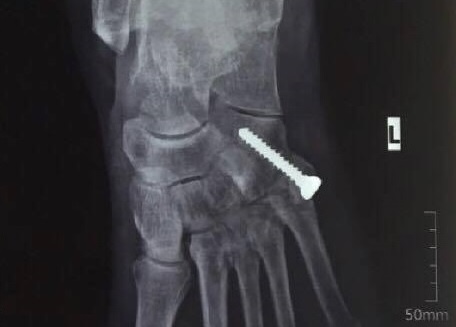

Bệnh nhân phải chịu đau đớn suốt 20 năm qua và uống hàng chục kg thuốc giảm đau chỉ vì một chấn thương được giấu kín.